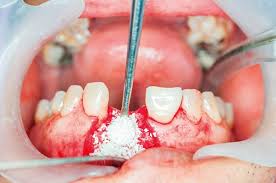

상악동거상술 보조

상악동거상술 시 자가치아를 이식재로 활용하여 효과 극대화

주요 장점

- 우수한 골형성

- 빠른 치유 속도

- 합병증 최소화